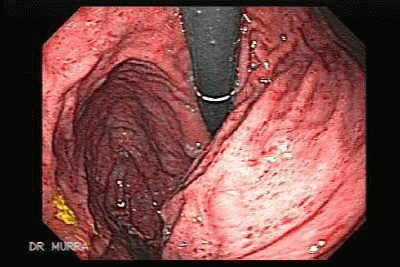

Самым информативным исследованием является гастроскопия. Зонд, вводимый в желудок пациента, дает возможность составить полную клиническую картину. Врач четко видит характер поражения стенок желудка и область распространения воспаления. Для исследования тканей пищеварительного органа может проводиться гистология.

Основой исследования является изучение внутренних органов с помощью зонда. Больному назначается осмотр и консультация у профильных специалистов для выявления болезней, которые могли спровоцировать обострение. Комплексная диагностика позволяет точно отделить гастрит от язвы или онкологического заболевания. Лечение хронического гастрита нужно начинать сразу после окончания исследования, чтобы не допустить сильных осложнений и избавить больного от страданий.